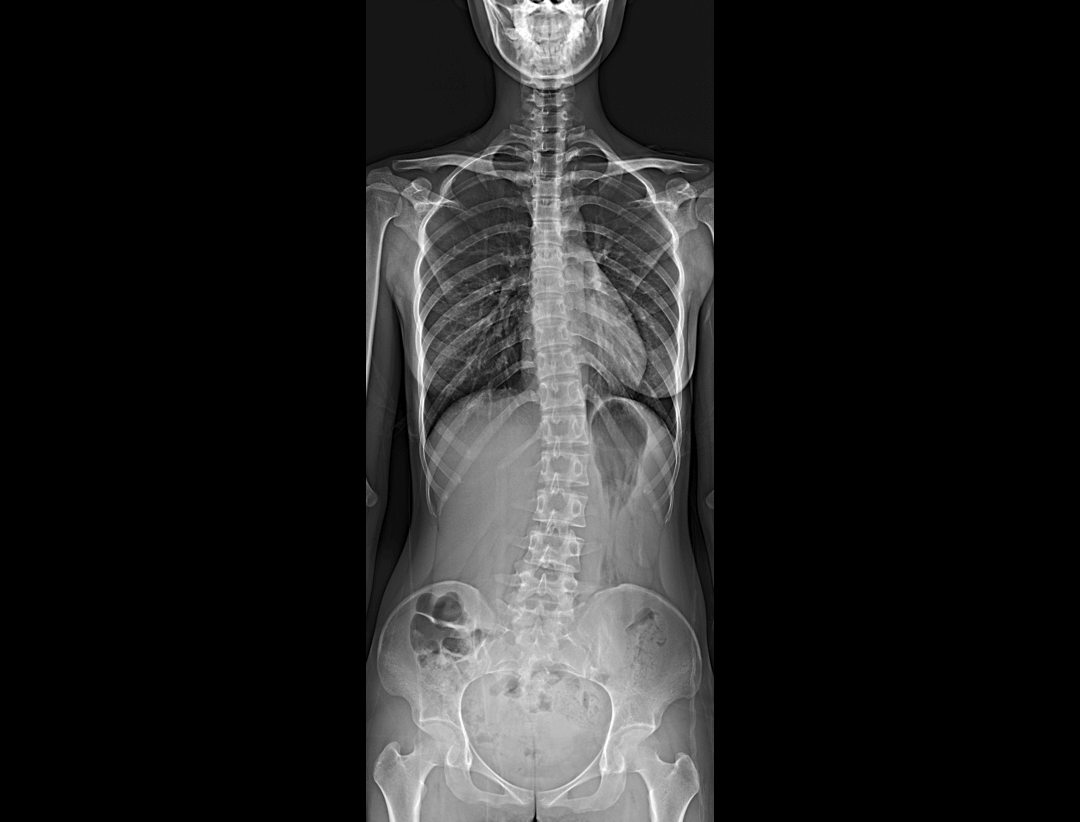

全自动无尺全景拼接

支持自动立位及卧位无尺全景拼接,为骨科、整形外科提供高质量全景影像。

测量功能*

集成脊柱Cobb角及股骨颈干角测量功能,精准指导外科手术及术后评估。

全脊柱正位、侧位